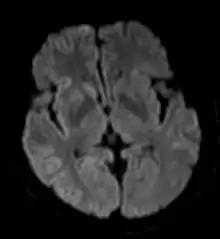

التصوير ذوالثقل بالانْتِشار DWI

- التصوير ذوالثقل بالانْتِشار (بالإنجليزية: Diffusion weighted imaging) [3] هو شكل من أشكال التصوير بالرنين المغناطيسي، حيث يتم التصوير بناء على قياس الحركة البراونية العشوائية لجزيئات الماء داخل فوكسل (عنصر حجمي) من الأنسجة. العلاقة بين الأنسجة والإنتشار معقدة، ولكن بصفة عامة، الأنسجة الخلوية الكثيفة أو المتورمة لديها معامل انتشار منخفض، وبالتالي يكون تصوير الإنتشار مفيد بشكل خاص في توصيف الورم واحتباس الدم في المخ [5].

صورة لدماغ مريض ، مأخوذة بتقنية التصوير ذوالثقل بالانْتِشار DWI. هذا المريض ظهرت له أعراض متزايدة و متسارعة من الخرف (dementia) (الذي هو تدهور مستمر في وظائف الدماغ ينتج عنه اضطراب في القدرات الإدراكية)، مع الهلوسة الأولية وتغير في السلوك. تَقَدّم المرض إلى حالة تعذر الحركة مع رَمَعٌ عَضَلِيّ (myoclonus). أظهر مخطط كهربية الدماغ (EEG) موجات حادة دورية على نطاق واسع. وتُظهر صورة الرنين المغناطيسي المأخوذة بتقنية التصوير ذوالثقل بالانْتِشار DWI إشارة عالية في القشرية الدماغية والجسم المخطط، بما يتفق مع تشخيص مرض كروتزفيلد جاكوب (sCJD) من النوع المتقطّع.